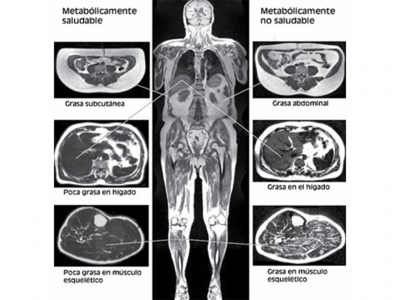

•    Tomografías (TAC) o resonancias magnéticas (RMN):

Para medir la grasa corporal también se pueden utilizar métodos como las tomografías y resonancias magnéticas.

Estos escaneos de imágenes transversales “pueden proporcionar las mediciones de composición corporal más precisas”.

Más allá de su gran precisión e inclusive determinación de la ubicación de la grasa visceral, es un método muy costoso, y no se suele utilizar con este propósito.